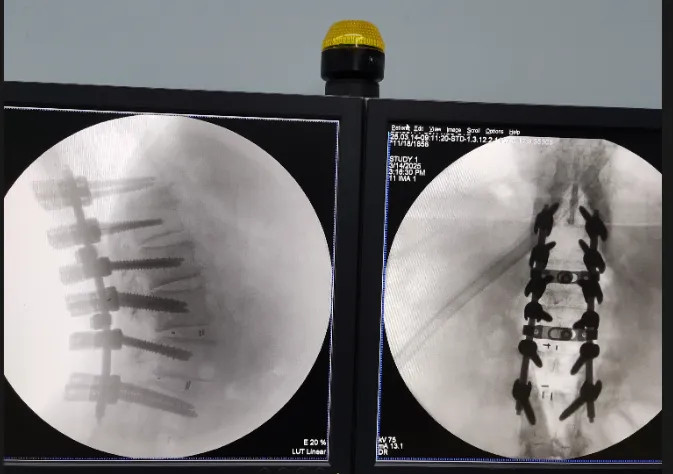

(术中C臂透视下精准操作场景)

(术后透视)

3月14日,在Stryker公司特别调拨的初代Opus专用工具护航下,林翔团队历时6小时完成胸椎管扩大减压+腰椎翻修+脊柱矫形三大术式整合。当看到患者术后即刻恢复足部活动时,整个医护团队都露出了欣慰笑容。